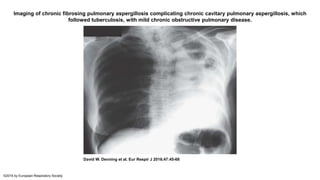

Chronic fibrosing pulmonary aspergillosis

• CFPA is often an end result from untreated CCPA. Extensive fibrosis with

fibrotic destruction of at least two lobes of lung complicating CCPA, leading

to a major loss of lung function.

• Usually the fibrosis is solid in appearance, but large or small cavities with

surrounding fibrosis may be seen. Serological or microbiological evidence

implicating Aspergillus spp. is required for diagnosis. One or more

aspergillomas may be present

• The onset of CFPA is heralded by complaints of worsening shortness of

breath, chest tightness, weight loss, and malnutrition.

• Radiographic imaging typically reveals extensive pulmonary fibrosis in one

or both upper lobes near the sites of known cavities and aspergillomas. In

many cases, the fibrosis progresses to involve an entire lung, which can

result in a 'white-out' of an entire lung or a 'destroyed lung' appearance

Imaging of chronic fibrosing pulmonary aspergillosis complicating chronic cavitary pulmonary aspergillosis, which

followed tuberculosis, with mild chronic obstructive pulmonary disease.

David W. Denning et al. Eur Respir J 2016;47:45-68

©2016 by European Respiratory Society

• #23 Imaging of chronic fibrosing pulmonary aspergillosis complicating chronic cavitary pulmonary aspergillosis, which followed tuberculosis, with mild chronic obstructive pulmonary disease. Complete opacification of the left hemi-thorax developed between February 1998, when a left upper lobe cavity with a fluid level was present, and May 1999. Multiple left lung autopsy percutaneous biopsies showed evidence of chronic inflammation, but no granulomas or fungal hyphae.